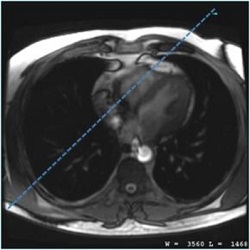

2. On the axial or axial-oblique localizer, prescribe a vertical long-axis scan plane of the right chambers.

Figure 1. Example of slice position